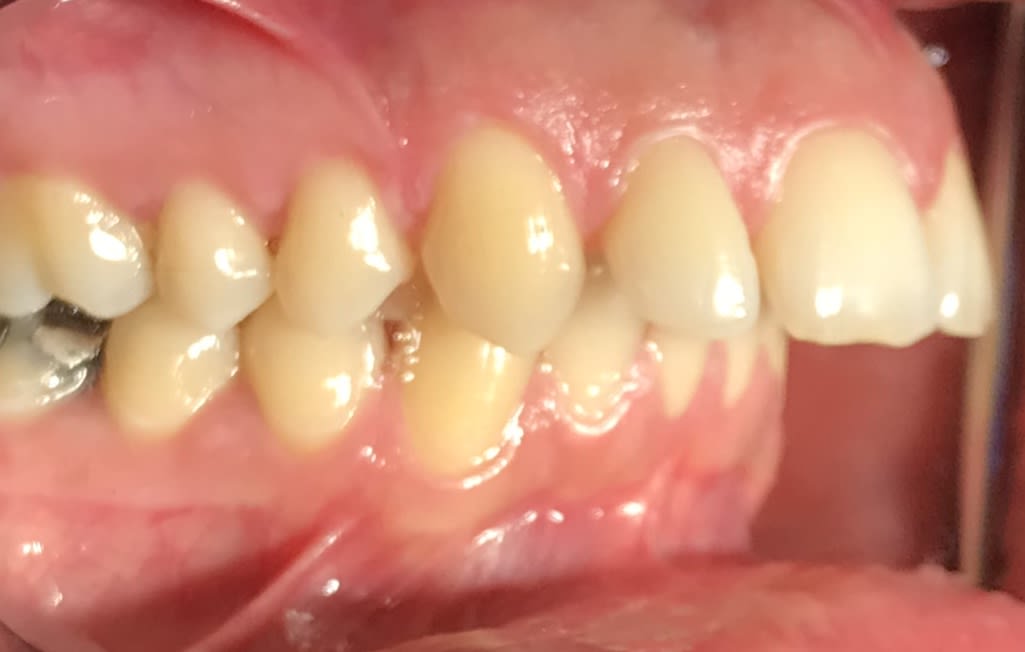

J’ai Algi qui est passé au cabinet avec son problème de classe II . Il a mal à la nuque , et aux temporaux .